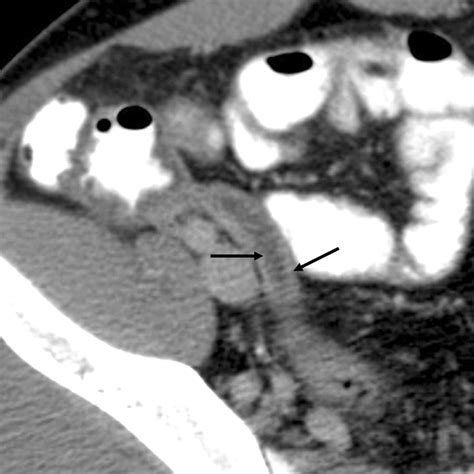

Radiologists look for specific markers when evaluating a CT scan for appendicitis. These indicators are crucial for confirming an acute inflammatory process within the appendix. The following findings are commonly associated with the diagnosis:

• Appendix Diameter: A normal appendix is typically 6 millimeters or less in diameter. If the diameter exceeds this threshold, it is a primary indicator of distention and inflammation.

• Wall Thickening: Inflammation causes the muscular wall of the appendix to thicken. This is often highlighted when intravenous contrast dye is used.

• Periappendiceal Fat Stranding: This appears as hazy, gray density surrounding the appendix, indicating that the inflammation has begun to spread into the surrounding fatty tissue.

• Appendicoliths: These are calcified deposits (fecal stones) within the appendix that can obstruct the lumen, leading to infection.